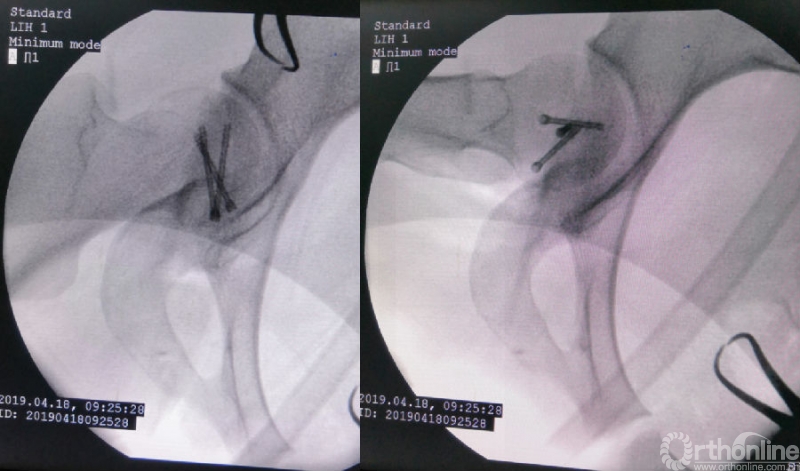

术中资料

对横跨切口远端的旋股内侧动脉血管束应特别注意,其自股骨颈的前方经内侧绕至后方延伸为旋股内侧动脉深支,是股骨头血供的主要来源。

术后影像学资料

术后1年